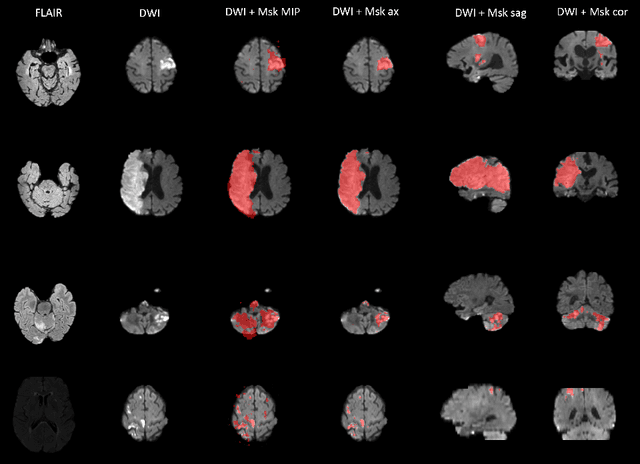

Abstract:Magnetic resonance imaging (MRI) is a central modality for stroke imaging. It is used upon patient admission to make treatment decisions such as selecting patients for intravenous thrombolysis or endovascular therapy. MRI is later used in the duration of hospital stay to predict outcome by visualizing infarct core size and location. Furthermore, it may be used to characterize stroke etiology, e.g. differentiation between (cardio)-embolic and non-embolic stroke. Computer based automated medical image processing is increasingly finding its way into clinical routine. Previous iterations of the Ischemic Stroke Lesion Segmentation (ISLES) challenge have aided in the generation of identifying benchmark methods for acute and sub-acute ischemic stroke lesion segmentation. Here we introduce an expert-annotated, multicenter MRI dataset for segmentation of acute to subacute stroke lesions. This dataset comprises 400 multi-vendor MRI cases with high variability in stroke lesion size, quantity and location. It is split into a training dataset of n=250 and a test dataset of n=150. All training data will be made publicly available. The test dataset will be used for model validation only and will not be released to the public. This dataset serves as the foundation of the ISLES 2022 challenge with the goal of finding algorithmic methods to enable the development and benchmarking of robust and accurate segmentation algorithms for ischemic stroke.